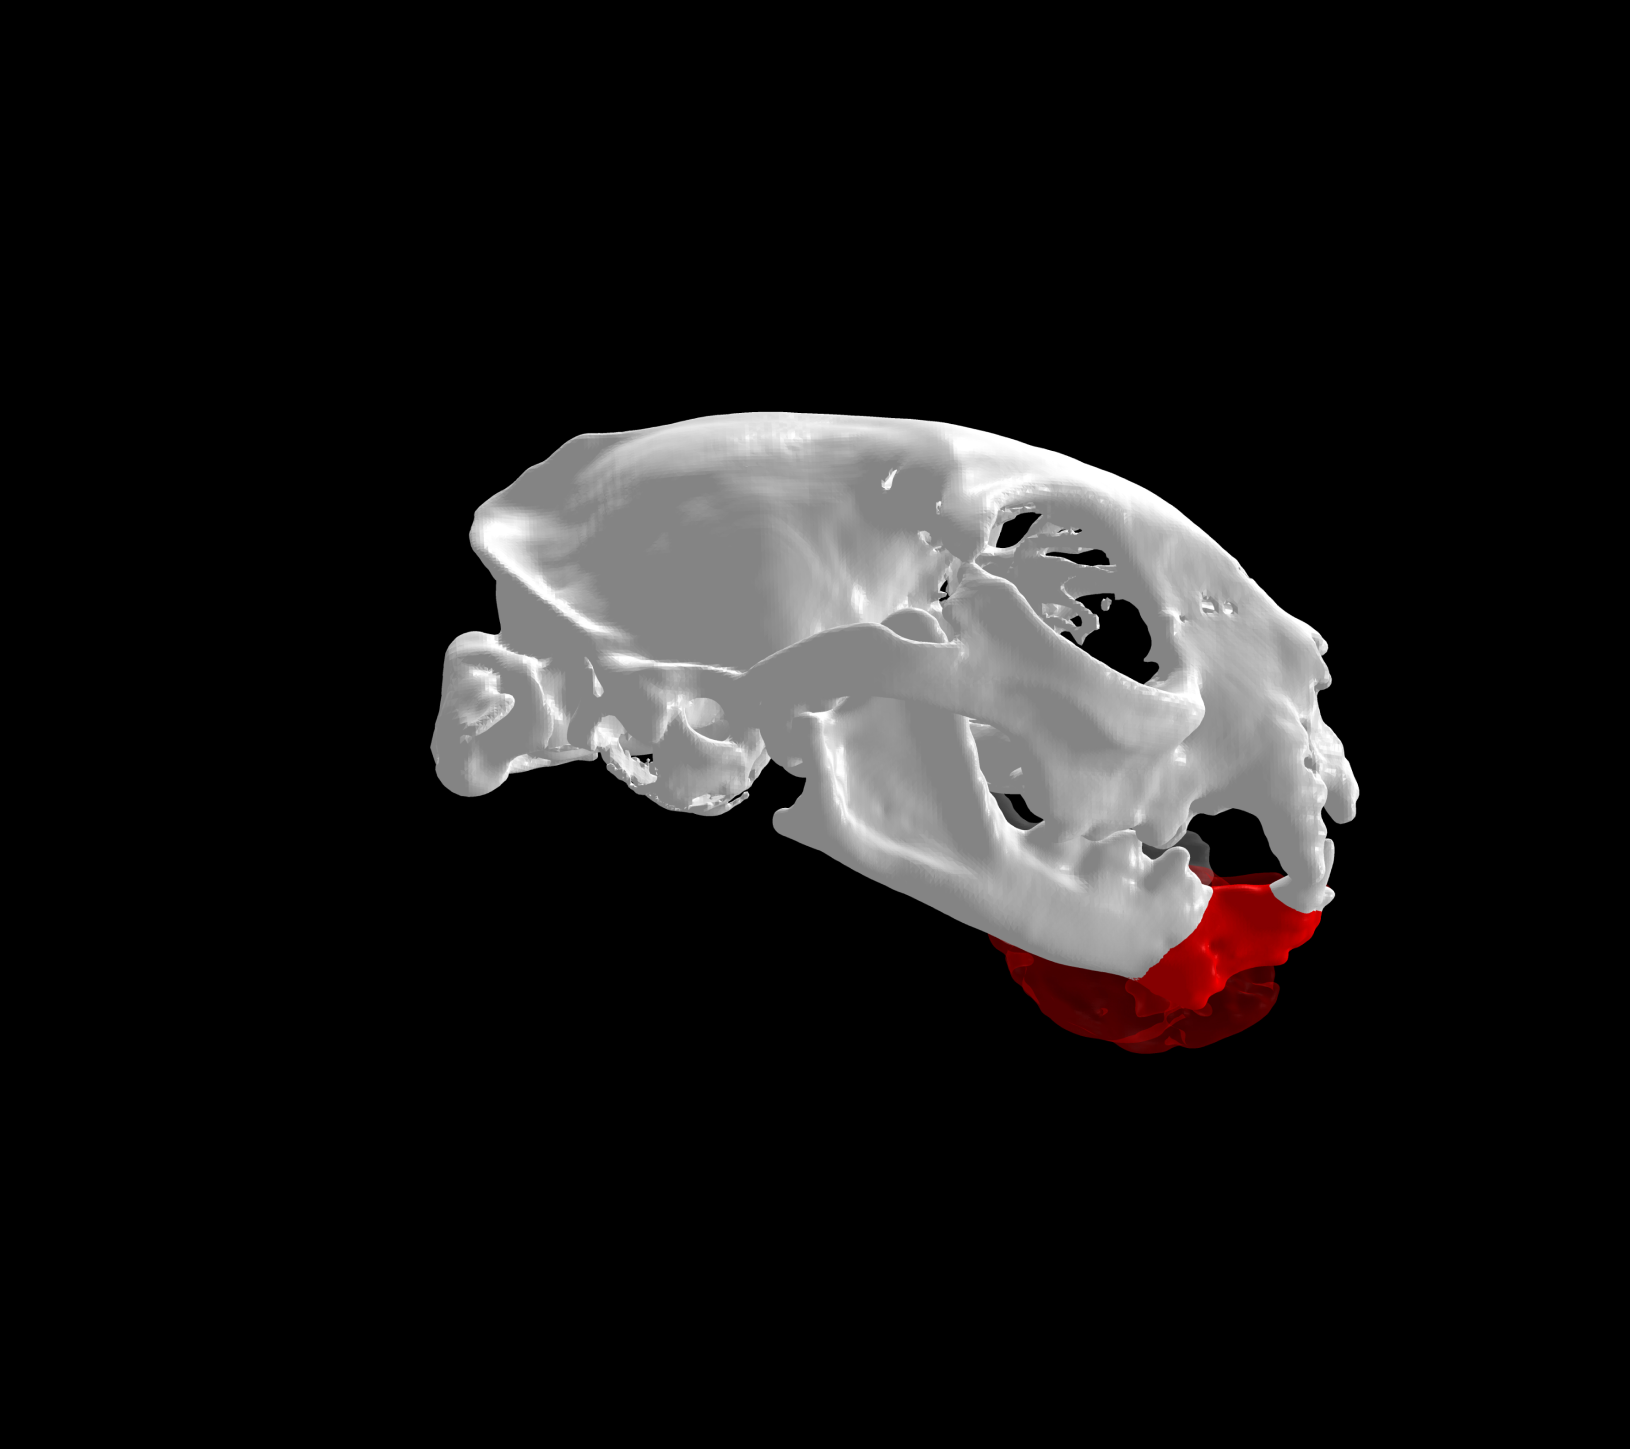

La customización de implantes quirúrgicos se refiere a la adaptación de los mismos a las necesidades de cada paciente, siendo personalizados a la anatomía única de cada individuo.

Esto se consigue gracias a los avances en la tecnología de fabricación, como la impresión 3D. Con esta tecnología se pueden crear implantes personalizados tanto en acero quirúrgico como en titanio a partir de imágenes médicas de tomografías computerizadas (TC) o resonancias magnéticas (RM).

- Mejor ajuste y adaptación al paciente: favorece la colocación precisa y la estabilidad del implante sobre la anatomía quirúrgica.